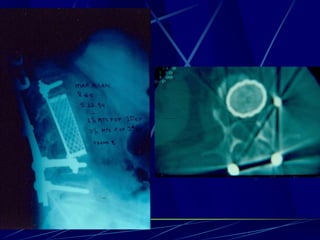

T.B.C.

Φυματίωση της σπονδυλικής στήλης